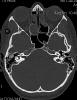

AVC amplio de territorio de A. cerebral media